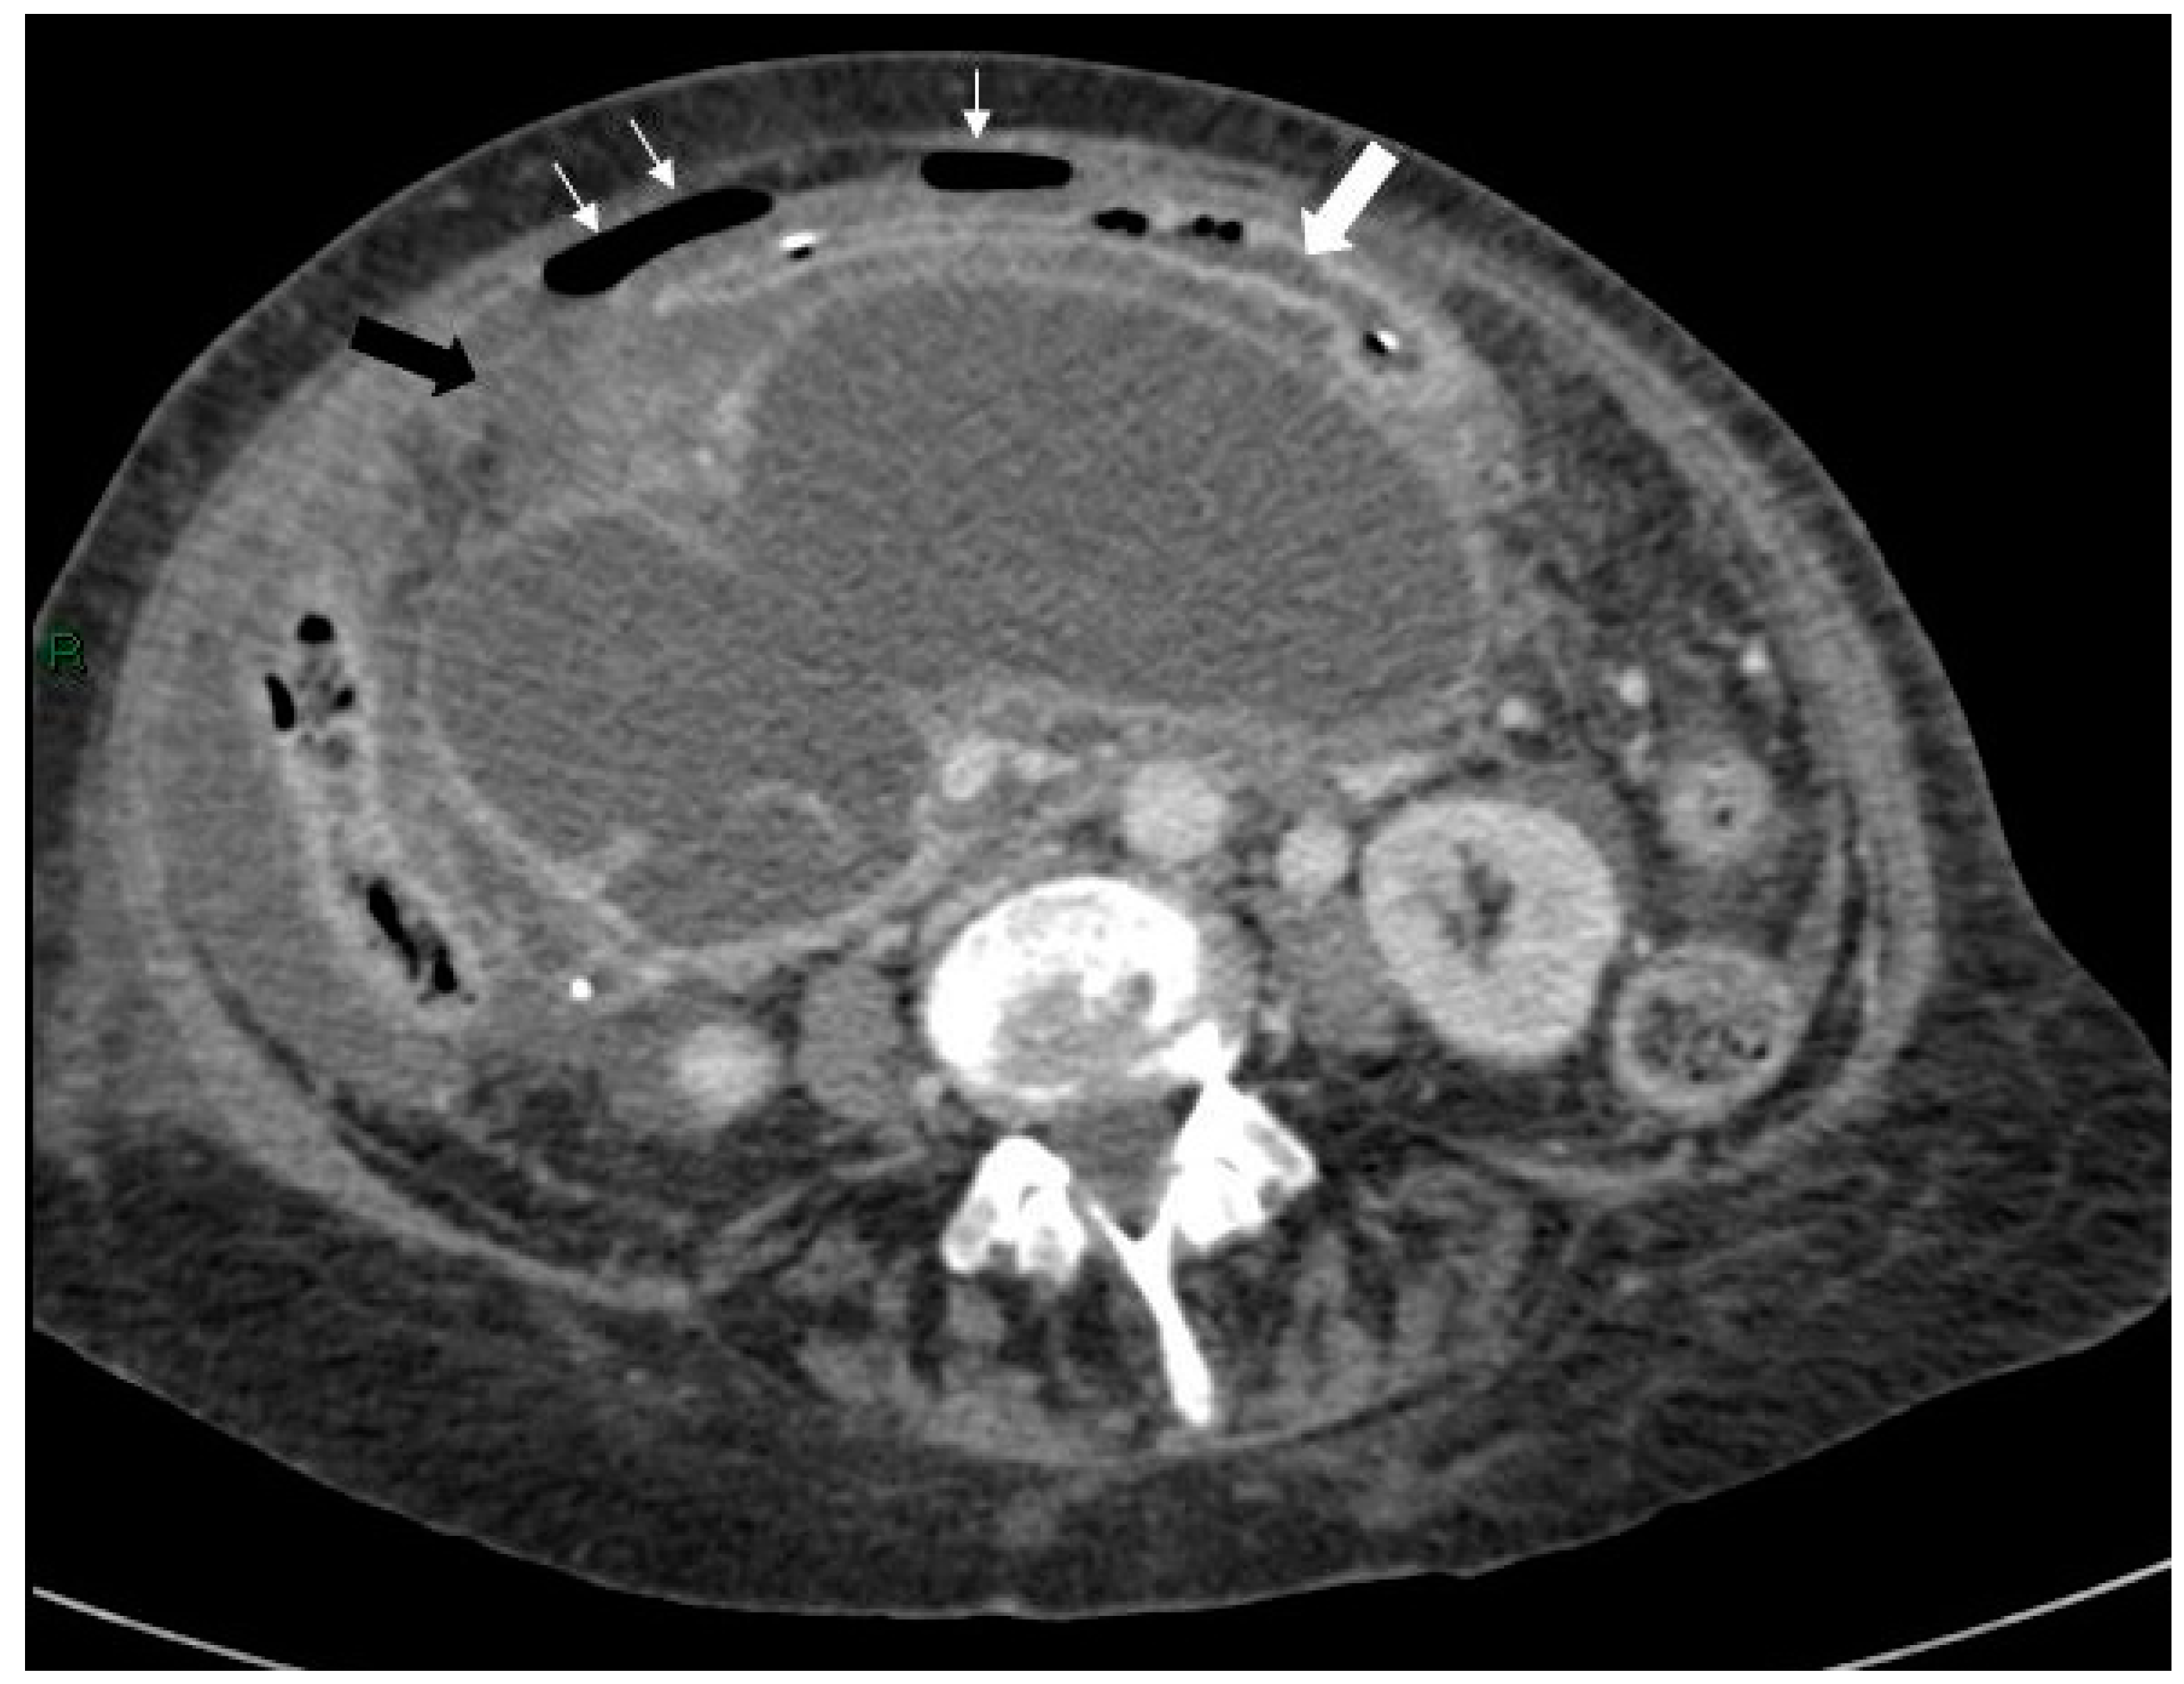

Figure 3.

Axial CT scan of the abdomen showing free air anterior to the liver (white arrows) and free fluid around the liver and spleen (black arrows).

Figure 4.

Axial CT scan of abdomen showing free air anterior to the liver (white arrows) and free fluid around the liver and spleen (black arrows).